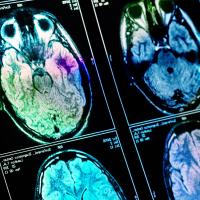

This article explores how deep learning can be combined with traditional techniques to improve medical images such as those produced by CT, MRI, and PET scans.

Quicker and smaller scanners would be a huge improvement, not only for your personal safety and scanning experience, but also for cutting NHS waiting lists. This is where artificial intelligence offers new possibilities. Riccardo Barbano, Alexander Denker, and Hok Shing Wong, from the Mathematics for Deep Learning (maths4DL) research programme, are three researchers who are exploring ways of deploying it in medical imaging. The aim is to come up with safe and reliable methods that improve the diagnostic value of imaging techniques while hopefully reducing the amount of radiation, and discomfort, that patients are exposed to.

Answers to such fundamental questions, often provided by academic researchers, power industrial developments. Indeed, a handful of companies are now offering CT and MRI scanners that use deep learning in the reconstruction of images. A more common use of AI in medical imaging is post-processing, which employs deep learning to improve images after they have been produced by traditional scanners. But while this helps clinicians with diagnoses, it doesn't speed up the scanning process or reduce the radiation patients are subjected to. It will probably some time yet until scanners with in-built AI features are routinely used.